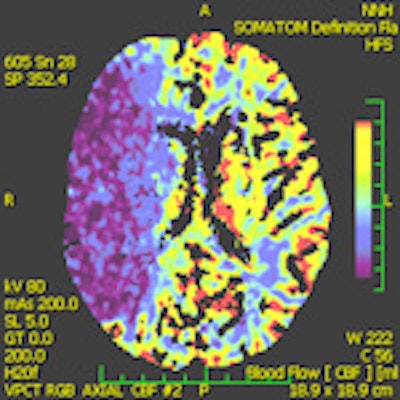

A 28-year-old male with a history of aortic valve replacement and poor compliance with anticoagulative medication, presented with sudden left-sided hemiplegia. No penumbra was apparent on perfusion CT, as shown in left figure (CBF) and middle figure (CBV). Standard CT image (right figure) two days following decompressive craniectomy shows significant mass effect with dislocation of midline structures. Images courtesy of Dr. Josef Vymazel.When ultrafast CT scanners covering almost the entire brain are used, the potential to detect ischemia and salvageable tissue is very similar to MRI. However, the major drawback of CT is the high radiation dose, while in MRI it is the more complicated and time-consuming aspect of the examination, he wrote in an article published online on 29 September by Insights into Imaging.

"The introduction of perfusion CT (PCT) of the brain has significantly improved the sensitivity and specificity in detecting fresh ischemia. Perfusion deficit can be detected immediately after stroke, i.e., in the time when a standard CT is still negative," Vymazal stated.

Different parameters are used in routine clinical practice for the detection of penumbra with CT and MRI. The subtraction of cerebral blood flow (CBF) and cerebral blood volume (CBV) is the usual way to detect penumbra using CT, according to the authors. On MRI, a subtraction between perfusion parameters (mean transit time, time to peak, or CBF) and diffusion-weighted imaging, rather than CBV, is used because CBV (especially on MRI) is not sensitive enough to detect small lesions. Such lesions are easily detected with DWI, according to the authors. DWI, on the other hand, may underestimate the final stroke volume and grows into CBV over the time.